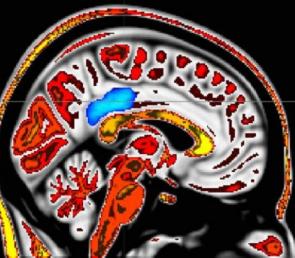

CORTEZA CINGULADA MENOS ACTIVA

Un total de 76 voluntarios sanos y que nunca habían meditado completaron el cuestionario de consciencia plena de Friburgo. A continuación, los autores aplicaron un estímulo térmico doloroso (49o C) a los probandos mientras registraban la actividad de su cerebro mediante tomografía por resonancia magnética funcional. Las neuroimágenes revelaron que una mayor disposición a la consciencia plena durante la exposición al calor doloroso se asociaba con una mayor desactivación de la corteza cingulada posterior, una región cerebral que participa en la red neuronal por defecto. En los sujetos que indicaban que sentían un dolor notable, en cambio, esta área cerebral se mostraba más activa.

La red neuronal por defecto se extiende desde la corteza cingulada posterior hasta la corteza prefrontal medial del cerebro, áreas que se hallan en continua interacción. Esta red se encuentra relacionada con el procesamiento de los sentimientos del yo y de la mente que divaga, explica Zeidan en un comunicado de prensa. «El modo por defecto se desactiva cada vez que se realiza cualquier tipo de tarea, como leer o escribir, y se reactiva cuando se deja de efectuar la tarea; también se revierten pensamientos, sentimientos y emociones que se autorrelacionan. Los resultados de nuestro estudio demuestran que las personas "conscientes" están menos atrapadas en la experiencia del dolor».

Según los autores, el estudio aporta información neurobiológica novedosa, puesto que revela que las personas con puntuaciones de consciencia plena más altas presentan una activación menor de las regiones centrales relacionadas con la red por defecto (corteza cingulada posterior, entre ellas) y experimentan menos dolor. En los sujetos con una capacidad menor de consciencia plena, sucede a la inversa. Por ello, la atención plena y la corteza cingulada posterior deben considerarse para la creación de terapias contra el dolor, concluyen. Zeidan añade: «A partir de investigaciones anteriores, sabemos que una persona puede aumentar su capacidad de consciencia plena mediante el entrenamiento de este tipo de meditación, por lo que esta podría ser una forma efectiva para alivar a los millones de personas que sufren dolor crónico».